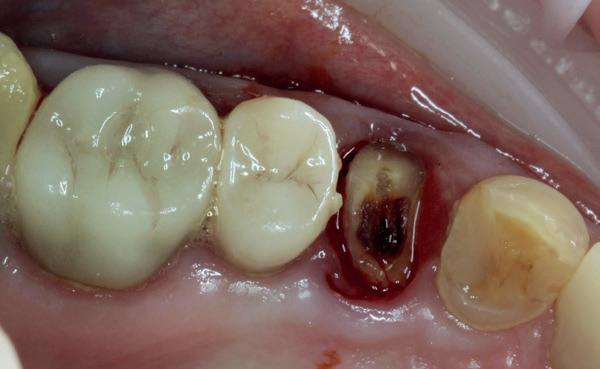

De aanleiding: waarom brak de kies?

De patiënt kwam bij mij in de praktijk met een afgebroken eerste premolaar 24. Op het eerste gezicht leek het een typische casus van structurele verzwakking, mogelijk door een oude restauratie of een occlusale overbelasting. Maar een nadere analyse toonde een veel fundamenteler probleem: er was geen hoektandgeleiding aanwezig.

Normaal gesproken neemt de cuspidaat de functie van disclusie over bij laterale bewegingen, waardoor premolaren en molaren worden ontzien van over-

matige zijwaartse krachten. Bij deze patiënt functioneerde de eerste premolaar echter als een canine, wat betekende dat hij continue laterale belasting kreeg waarvoor hij simpelweg niet ontworpen was. De breuk was dan ook geen toeval, maar een voorspelbare mechanische uitkomst van een verkeerde krachtenverdeling.

In een ideale situatie zou ik eerst de occlusale verhoudingen corrigeren voordat ik een implantaat plaatste. Maar zoals vaak in de praktijk, had de patient een duidelijke wens: een snelle, vaste oplossing, zonder aanvullende restauratieve behandelingen zoals het herstellen van de hoektandgeleiding.

1. Afgebroken 24. Geen hoektandgeleiding aanwezig.

De implantaatplaatsing en de beslissende fout (afbeelding 1-13)

De extractie verliep voorspoedig, waarbij ik zoals al-

tijd probeerde de buccale botlamel intact te houden. Dit is cruciaal voor latere botbehoud en implantaatplaatsing. Na curettage en spoelen van de alveole beoordeelde ik de situatie opnieuw: de botcondities leken gunstig voor een immediaat implantaat.